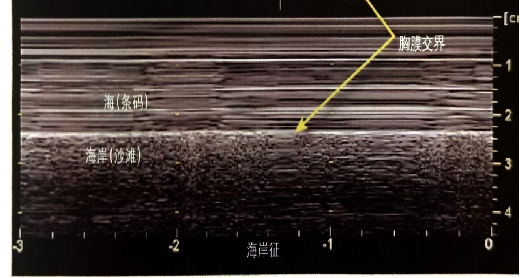

肺滑动征:①肋骨下高回声、光滑的水平线为胸膜;②正常情况下,脏、壁层胸膜紧贴,随呼吸相对滑动;③粘连或者有气体分隔脏、壁层胸膜时,胸膜滑动减弱或消失。在M型超声下的肺滑动征称“海岸征”,能更好地观察肺滑动征。肺滑动和海岸征的存在基本可以排除气胸(视频2,图7)。

图片

图7  海岸征

A线:正常肺征象的一部分,是与胸膜线平行的重复伪影,A线之间的间距等于皮肤到胸膜线之间的距离,A线出现却不伴有肺滑动征,则提示气胸的存在视频2